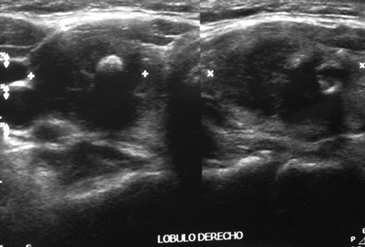

Paciente de sexo femenino, 61 años, con antecedentes de hipertensión arterial y dislipidemia. Estando asintomática, en control médico se pesquisa TSH disminuida por lo que fue derivada a endocrinología. Al examen físico destacaba a la palpación tiroidea un nódulo derecho, duro, móvil, no doloroso. El perfil hormonal confirma un hipertiroidismo subclínico (TSH 0,07 μUI/mL y T4L 1,33 ng/dL). Se solicita ecotomografía tiroidea que demuestra un bocio multinodular destacando un nódulo dominante en el lóbulo derecho, hipoecogénico, mal delimitado, asociado a gruesas calcificaciones, de 17,9 x 27,1 mm, con flujo al doppler color (Figura 1 y 2). Se realizó un cintigrama tiroideo que evidenció un nódulo hipercaptante en el lóbulo derecho con supresión parcial del resto del parénquima glandular; probablemente responsable del hipertiroidismo subclínico. Se solicita PAF del nódulo dominante cuyo resultado fue compatible con un carcinoma papilar tiroideo. La paciente se somete a tiroidectomía total, la cual se realizó sin incidentes. El resultado de la biopsia fue un carcinoma papilar, unifocal, variedad oncocítica tipo Warthin de 2,2 x 1,7 cm; el tumor no se extendía a tejidos peritiroideos, ni alcanzaba los bordes quirúrgicos, pero sí se observaban permeaciones vasculares tumorales (Figura 3). Recibió 100 mCi de yodo radioactivo (con TSH 90,12 μUI/mL, T4L 0,21 ng/dL, Tiroglobulina 2,8 ng/mL y anticuerpos antitiroglonbulina 1 UI/mL). La exploración sistémica evidenció una moderada a intensa captación en región anterior del cuello en relación al lecho tiroideo; el resto del cuerpo se apreciaba de distribución normal y no se evidenciaban imágenes sugerentes de metástasis extracervicales. La paciente inicia tratamiento con levotiroxina. En el control de los 6 meses la paciente se encontraba en buenas condiciones generales y asintomática, la ecografía cervical no mostraba evidencia de recidiva local, la tiroglobulina estaba indetectable (< 0,5 ng/mL) y los anticuerpos antitiroglobulina se mantenían negativos (1 UI/mL).